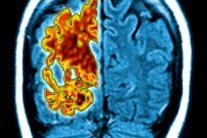

إيلاف:& كشف باحثون أميركيون عن أن السيدات أكثر عرضة للإصابة ببروتينات خبيثة في الدماغ تزيد من خطر تعرضهن للزهايمر. كما وجد الباحثون من خلال دراسة أجروها بهذا الخصوص على 300 شخص مسن أن نسب بروتيني تاو وبيتا اميلويد الذين يسببان الحالة المرضية تقل بشكل واضح عند الرجال مقارنة بالسيدات.

وقال الباحثون إنه حين يتجمع هذين البروتينين على هيئة تشابكات أو كتل، على التوالي، فإنهما يدمران الخلايا العصبية، ما يؤدي للإصابة بفقدان في الذاكرة وتشوش.

وأوضح الباحثون في نفس السياق أن تلك البروتينات توجد في كل المادة الرمادية ولا تتسبب في حدوث مشكلة إلا عندما توجد بكميات كبيرة. ونقلت صحيفة الدايلي ميل البريطانية عن دكتور ريزا سبيرلينغ، الباحثة الرئيسية بالدراسة من مستشفى ماساتشوستس العام، قولها "تشير أدلة بحثية متزايدة إلى أن السيدات قد يكن أكثر عرضة لبعض التغييرات الفسيولوجية المرتبطة بمرض الزهايمر، وهو ما قد يسلط الضوء من جديد عن السر وراء أن اثنين من كل ثلاثة مصابين بمرض الخرف إناث".